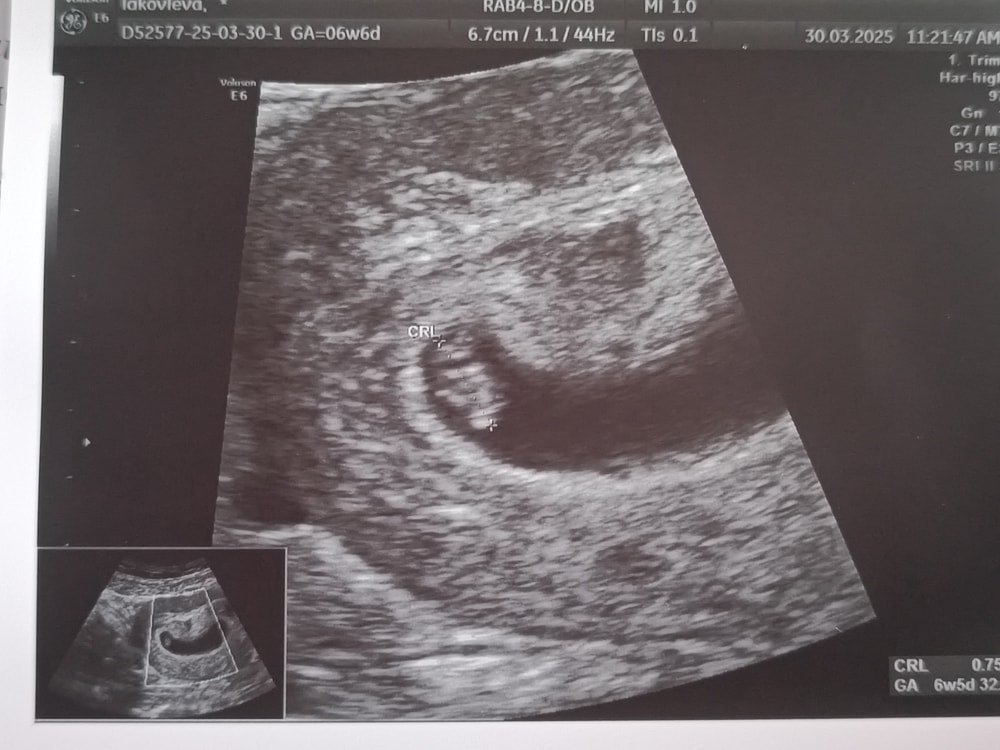

Первое УЗИ